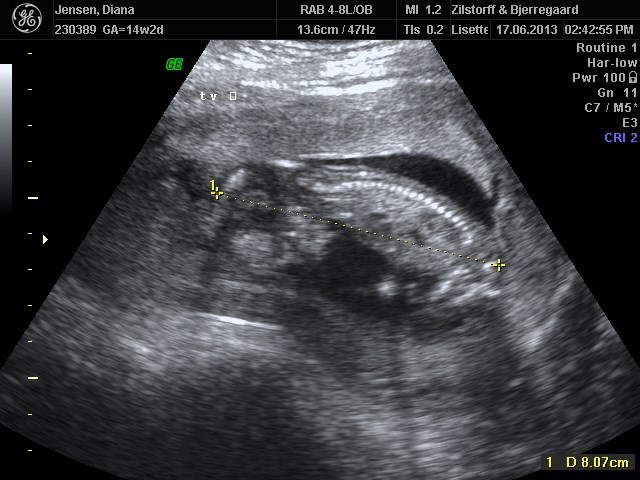

og self. kommer der lidt billeder

tvilling 1 først og tvillinge 2 næste og samme med mål